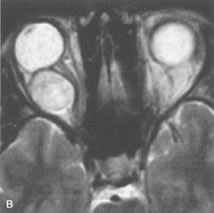

Tl relaxation time is the time required for the energized nuclei to give up the excess energy that was acquired from the RF pulse (high-energy state) and re-establish equilibrium (low-energy state) with the main magnetic field. The excess energy is released by these excited nuclei to the surrounding molecular environment, or lattice, and results in T1 relaxation, also called spin-lattice relaxation time. In different biologic tissues, hydrogen has a Tl ranging from a few hundred milliseconds to a couple of seconds. This range exists because local tissue factors affect the ability of specific protons to give up energy to the surrounding tissues. For example, hydrogen atoms attached to the carbon atoms of fat molecules relax much more rapidly than those attached to the oxygen atoms of water molecules. Viscosity, concentration, temperature, and molecular environment of the hydrogen atoms in the tissues also affect the T1 relaxation time. On a T1-weighted orbital image, fat, which has a very short T1 relaxation time, yields a high-intensity signal; the rectus muscles, which have an intermediate T1, yield an intermediate-intensity signal; and the vitreous, which has a long T1, yields a low-intensity signal (Fig. 8).5,8,16